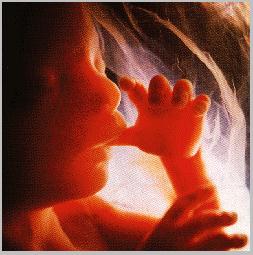

A criança não-nascida com sete semanas (5 semanas depois da concepção)

“Há uns anos atrás, ao dar uma anestesia por causa de uma ruptura da trompa de falópio numa gravidez (aos dois meses), deparei-me com o que acreditei ser o ser humano mais pequeno alguma vez visto. O saco embrionário estava intacto e transparente. Dentro do saco estava um minúsculo rapaz humano, nadando vigorosamente dentro do líquido amniótico, estando agarrado à parede uterina pelo cordão umbilical. O minúsculo ser humano estava perfeitamente desenvolvido com dedos longos e suaves, pés e unhas. A sua pele era quase transparente e as artérias delicadas e as veias eram proeminentes até ao final dos dedos. O bébé estava perfeitamente vivo e não parecia, de maneira nenhuma, como as fotografias e os desenhos de “embriões” que eu tinha visto. Quando o saco foi aberto, o minúsculo ser humano imediatamente perdeu a vida e tomou a forma do que é aceite como a aparência de um embrião nesta fase, extremidades rombas, etc.

(Paul E. Rockwell, M.D.)